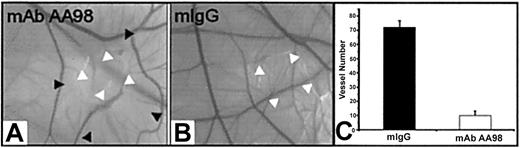

Inhibition of angiogenesis in CAM assays by mAb AA98

Activation, migration, and proliferation of endothelial cells play important roles in angiogenesis.1,2 We therefore investigated the effect of mAb AA98 on angiogenesis in the CAM assay. The function of CD146 in such experimental settings has not been addressed in previous studies. Placed on CAMs of day-6 embryos were 1, 5, 10, or 20 μg mAb AA98 or control mIgG absorbed on small filter disks. We used 20 embryos per group for mAb AA98 treatment and 10 embryos per group for mIgG treatment. After 12 hours of incubation, areas surrounding the applied mAb AA98 were nearly avascular. These avascular zones became larger with increasing incubation time. At 24 hours of incubation, the zone size reached about 10 mm2, and no evidence of any inflammatory reaction or hemorrhage was seen in the implant area (Figure 3A). In mAb AA98—treated CAMs, the frequency of avascular zones at the implantation sites was observed to increase with increasing amounts of antibody: 13 of 20 CAMs at 1 μg, 15 of 20 CAMs at 5 μg, 18 of 20 CAMs at 10 μg, and 20 of 20 CAMs at 20 μg. The mAb AA98—treated areas were conspicuous by the scarcity of sprouting or branching capillaries. Their blood vessel density was reduced approximately 7-fold compared with mIgG-treated CAMs (Figure 3C).

mAb AA98 inhibits angiogenesis in CAM assays. (A-B) CAM angiogenesis assays showing an almost avascular area in the CAM where the disk carrying 10 μg mAb AA98 was implanted and incubated for 24 hours (A). Normal vascularized CAMs were observed with 10 μg mIgG for 24 hours (B). White arrowheads point to implanted disk, and black arrowheads indicate the borders of the almost avascular area. (C) The number of small branching capillaries was counted within a defined area of 72 mm2surrounding the implanted disk. In each group, 10 embryos were used and the data represent the mean values (± SEM).